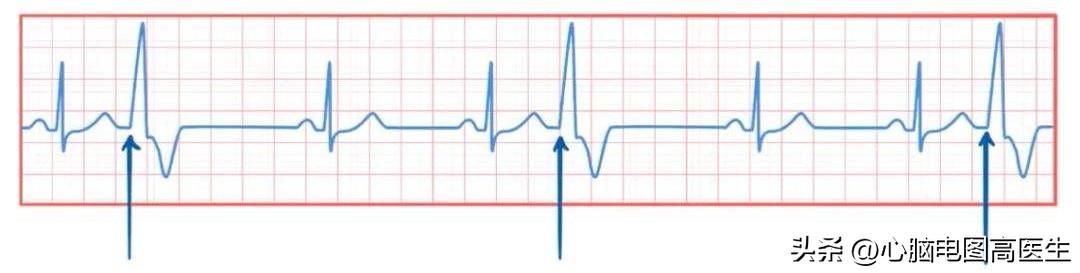

1.提前出现的QRS波群,宽大畸形,QRS波时限>0.12S,ST-T方向与主波方向相反。

2.QRS波群前后无相关P波。

3.代偿间歇多完全。

首先第一条,究竟多少算宽大?典型的室早,一般传导的时限>0.12S,表现在心电图上就是QRS波的宽度超过了三小格的距离。而且形态与正常的心搏明显不同。而后面的ST-T方向与主波相反,大家可以理解为因为除极的方向与正常不同,因此复极的方向也与正常不同,所以代表复极的ST段和T波也与正常的不同。

第二条,QRS波群前后无相关P波。可以理解为他是由心室发出的冲动,直接激动心室,由于交界区的存在,很难逆传到心房产生逆行的P波。但实际上,室早发生时,窦房结其实是不受影响的,所以他可以正常发出冲动控制心房,从而出现P波,但P波可能会重叠在室早的QRS波或T波上,从而不易辨认,因此叫做无相关P波,而不是无P波。考试的时候为了降低难度,室早的图一般是看不到P波的。

第三条,代偿间歇多完全。大家照旧先理解为早搏后心脏要歇歇,而完全的意思就是歇的时间比较长,因此可以看到室早后面距离下一个正常心搏一般都比较远。